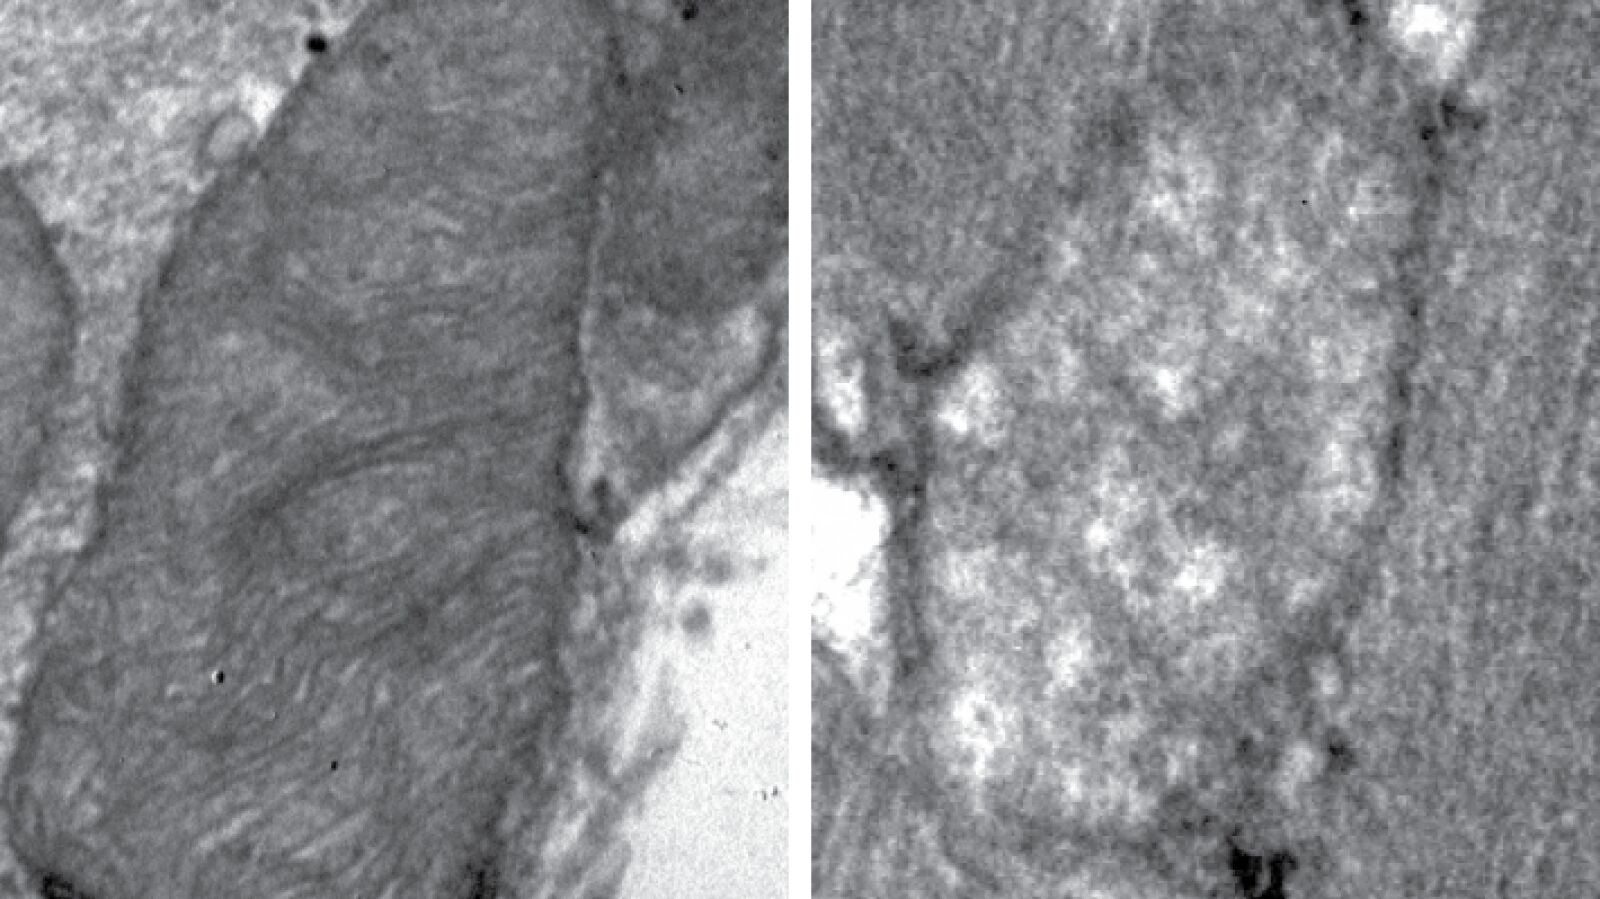

Mecanismos moleculares tras el envejecimiento muscular

La mitofusina 2 es una proteína mitocondrial que interviene en el buen funcionamiento de la dinámica de las mitocondrias dentro de las células, y tiene a la vez funciones relacionadas con la autofagia, un proceso crucial para la eliminación de mitocondrias dañadas. La pérdida de mitofusina 2 hace que el sistema de reciclaje de mitocondrias no funcione correctamente y, en consecuencia, se acumulen mitocondrias en mal estado en las células musculares.

Gracias al estudio, los investigadores también han identificado y descrito un sistema de rescate de la autofagia que entra en funcionamiento independiente de mitofusina 2, y que permite a las células recuperar parcialmente el sistema de reciclaje de mitocondrias en el músculo esquelético. Los científicos sugieren que esta podría ser una vía metabólica alternativa para aumentar la autofagia en el músculo esquelético y mantener un sistema de mitocondrias en mejores condiciones.